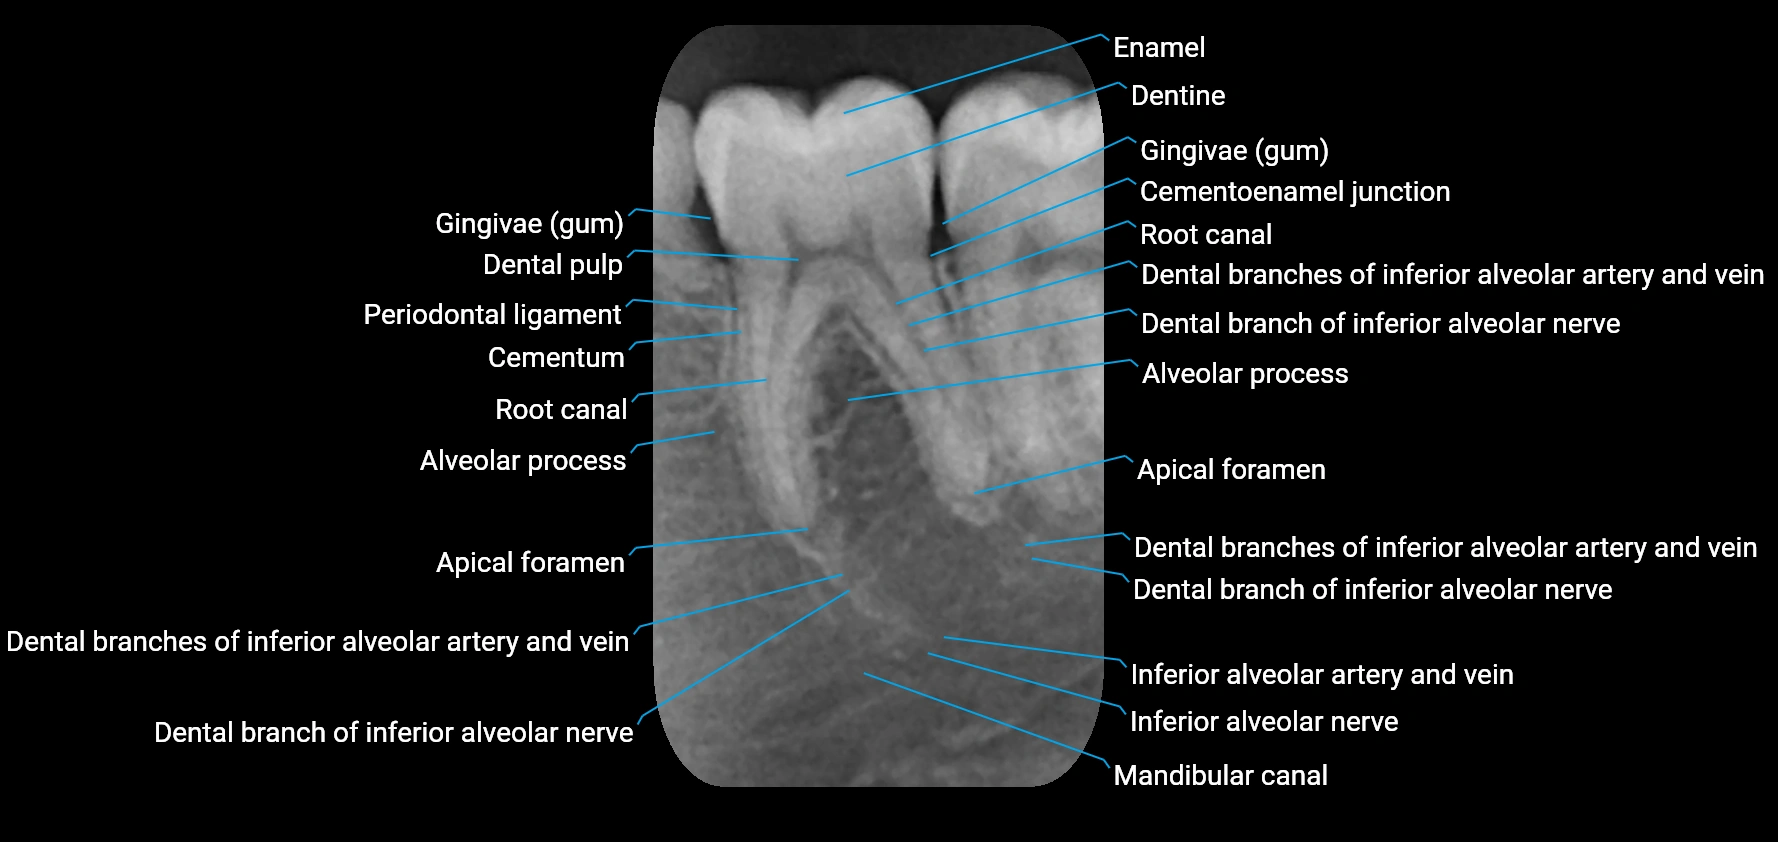

The alveolar process of the maxilla is the bony ridge of the maxilla that houses the upper teeth, extending from the anterior nasal spine to the maxillary tuberosity posteriorly. It consists of compact cortical bone on its outer surfaces and trabecular (cancellous) bone internally, with alveolar sockets (dental alveoli) forming individualized cavities for each tooth. The alveolar process develops in association with tooth eruption and resorption, adapting its shape and volume throughout life. It also forms part of the hard palate medially and contributes to the architecture of the midface, supporting the upper lip, cheeks, and nasal floor.

• Provides attachment for the periodontal ligament